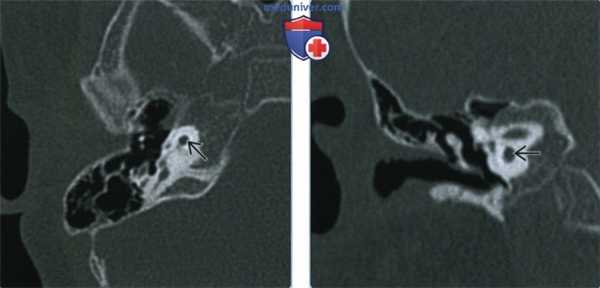

(Слева) При аксиальной КТ в костном окне у мальчика в возрасте 2,5 лет с глубокой двухсторонней врожденной нейросенсорной тугоухостью визуализируется маленькая бутонообразная структура, сопоставимая с гипоплазией улитки, изолированная от внутреннего слуховою канала (ВСК). Круглое окно отсутствует.

(Справа) При корональной КТ (реконструкция) у этого же пациента визуализируется маленькая зачаточная улитка (гипоплазия) без внутренней архитектуры.

2. КТ при гипоплазии улитки:

• КТ в костном окне:

о Изменения улитки:

- Различной степени выраженности, иногда асимметричные

- Маленькая улитка, обычно - Внутренняя структура улитки присутствует или отсутствует

- Единственный примитивный завиток или зачаточная форма

- Маленькая, кистозная, без стержня или межлестничной перегородки

- Маленькая, с внутренней архитектурой, с коротким стержнем

о Круглое окно: отсутствует или присутствует

о Канал улиткового нерва: отсутствует, сужен или расширен

о Внутренний слуховой канал: норма или сужение/аномалии

о Преддверие: норма, расширение, или гипоплазия

о Полукружные каналы (ПКК): норма, расширение, гипоплазия, отсутствие

о Водопровод преддверия: нормальный или увеличенный

о Канал лицевого нерва: аберрантый ход ± зияние

о Пространство и содержимое среднего уха: обычно норма